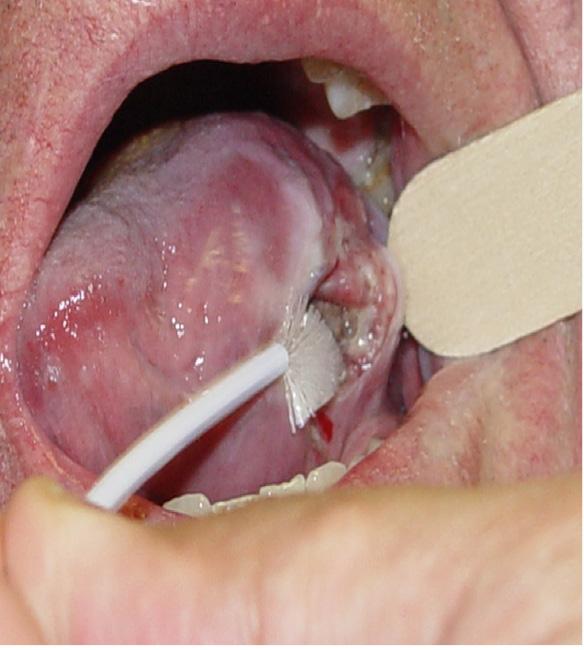

Cavidad oral: La presentación más frecuente es una lesión ulcerada o submucosa en la boca, cualquier lesión ulcerada, fácilmente sangrante en la cavidad oral que no desaparece con tratamiento sintomático en una semana debe de ser motivo de consulta y eventual biopsia; otros datos de alerta son la movilidad dental sin causa justificada, disartria, dolor en la irradiación de la primera rama del nervio trigémino, dificultad para movilizar la lengua (en etapas avanzadas), y sangrado de la cavidad oral. (Figura 2

Figura: 2. Lesión ulcerada, penetrante e infiltrante del borde izquierdo lingual, es ya una etapa avanzada. Cualquier lesión en boca que no desaparece con tratamiento tópico en una semana debe de ser evaluada por un especialista.